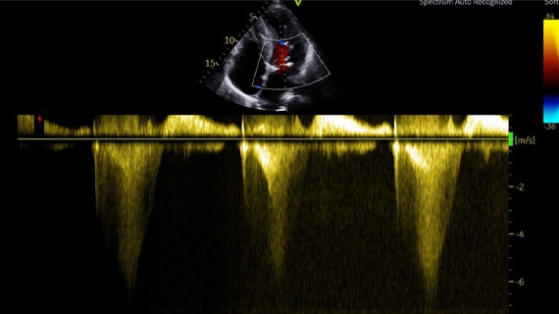

ETT : Gradient intra VG post alcoolisation, au repos

Le patient a été revu pour ETT + consultation à 6 mois en octobre 2019

• Il restait très symptomatique, avec une dyspnée NYHA III

• Le gradient intra-VG a été mesuré à 130 mmHg au repos, et l’IM semblait alors moyenne sur le SAM

• Tentative de relai de l’ATENOLOL par du NADOLOL 80 mg x 2/j, sans modifications sur le gradient ni les symptômes

• Décision de myomectomie chirurgicale